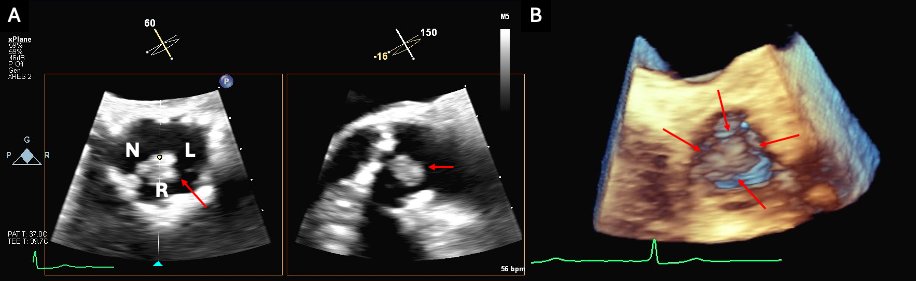

📝 Want to know contemporary & future options for the management of severe 2ndary MR? Check out this new JCF SotA Review to learn about TEER & emerging transcatheter MV repair & replacement devices here! 🔗bit.ly/4fbGuKY